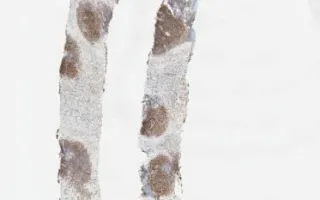

Soft Tissue, Follicular lymphoma, BCL6 stain

This slide shows BCL6 stain. H&E stain and immunohistochemistry for CD20, CD10, BCL2, and MIB1 are included in the Related Content section. MIB1 count was about 20%. The case was negative for CD5 and Cyclin D1 (also known as BCL1).